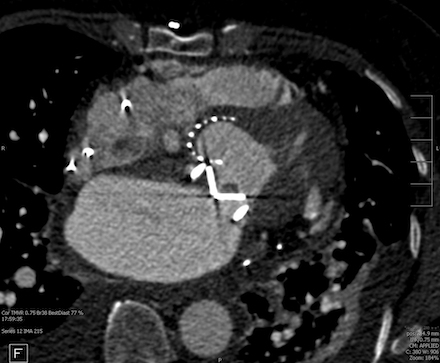

A 66 year old female with past medical history of rheumatic heart disease requiring mechanical mitral valve (MV) replacement on warfarin, HFpEF (EF 60%), atrial fibrillation requiring dual chamber pacemaker presented with worsening dyspnea on exertion. The patient was admitted for acute on chronic heart failure exacerbation requiring diuresis. Transthoracic echocardiogram (TTE) revealed significantly elevated gradients across the mitral prosthesis, concerning for significant prosthetic stenosis (peak velocity 2.4 m/s and mean gradient of 14 mmHg). Transesophageal echocardiogram (TEE) demonstrated moderate to severe mitral stenosis with a valve area of 0.6 sq cm by 3D planimetry, and poor leaflet excursion concerning for thrombus or pannus (Figure 1). Cardiac CT was suggestive of thrombus around the mechanical MV leaflets (Figure 2). Clinically, the patient had interval worsening heart failure symptoms and chest x-ray with worsening pulmonary edema. After consultation with cardiothoracic surgery, tPA was administered over 24 hours under close monitoring in the Cardiac Critical Care Unit. Repeat TEE post-thrombolysis showed improvement in MV area to 1.57 sq cm by 3D planimetry, with increased mobility of one mechanical MV leaflet (Figure 3). Persistent restriction of the other leaflet concerning for pannus remained, with no urgent surgical intervention indicated.